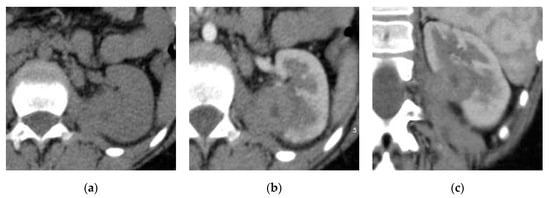

2.2. Renal and Perinephric Abscesses

| Renal abscesses | Round or geographic non-enhancing central fluid collection and enhancing rim. Perinephric fat stranding and thickening of Gerota’s fascia. |